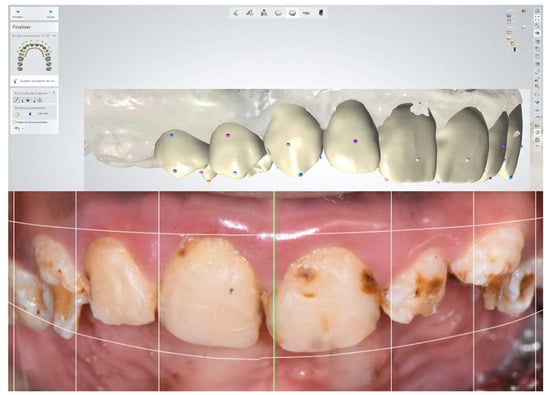

2.6.3. Intraoral Scanning for Digital Study Models

3.2. Digital Wax-Up and Use of CAD-CAM